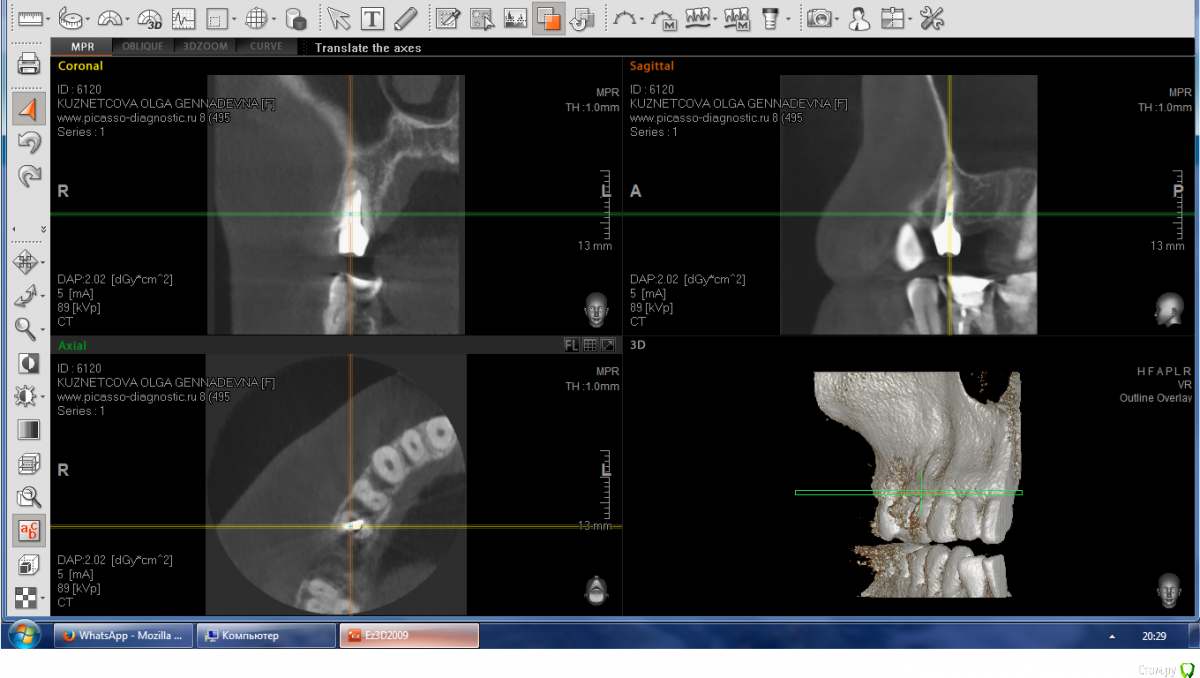

Allegro23 Опубликовано 11 ноября, 2016 Автор Поделиться Опубликовано 11 ноября, 2016 (изменено) КТ интересующей зоны, сделано 1 октября. Изменено 11 ноября, 2016 пользователем Allegro23 Ссылка на комментарий